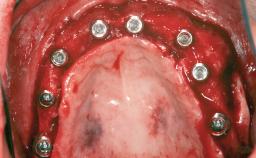

# of Implants 1

Bone Augmentation Staged|Vertical

Augmentation Materials Autogenous chips|Membrane